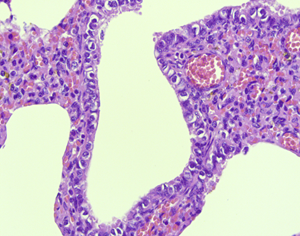

Nietypowe pożytki ze świń

Terminem „pożytki” określa się korzyści (materialne i niematerialne) czerpane z …